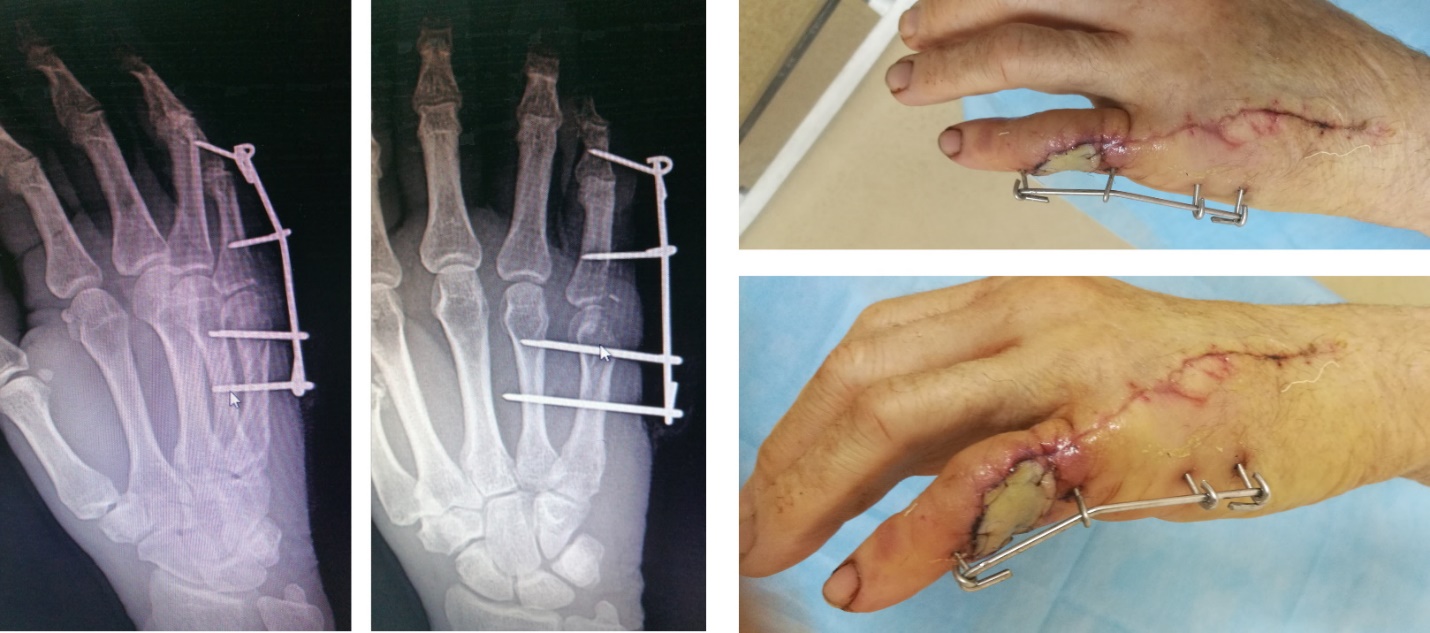

Данному пациенту не выполнены до операции рентгенограммы левой кисти – это пропущенный перелом. При ревизии раны не выявлен разрыв сухожилия разгибателя. И, как следствие, неправильная дальнейшая тактика врача: выполнен туалет раны антисептиком, наложены швы на кожу. В послеоперационном периоде развился отек, одна из причин – нестабильность отломков. Чрезмерное натяжение мягких тканей привело к некрозу тканей в области послеоперационной раны.

И что же дала такая тактика лечения?

А вот что.

Пациента пришлось брать через 10 дней на повторную операцию.

Было выполнено: иссечение нежизнеспособной ткани, свободная кожная пластика, остеосинтез V пястной кости и основной фаланги V пальца аппаратом наружной фиксации из К-спиц.

Это фото выполнено через 1 месяц после кожной пластики.

Пластика сухожилия выполнялась в отсроченном периоде через 4 месяца.

В итоге, пациент потерял 8 месяцев полноценной жизни.